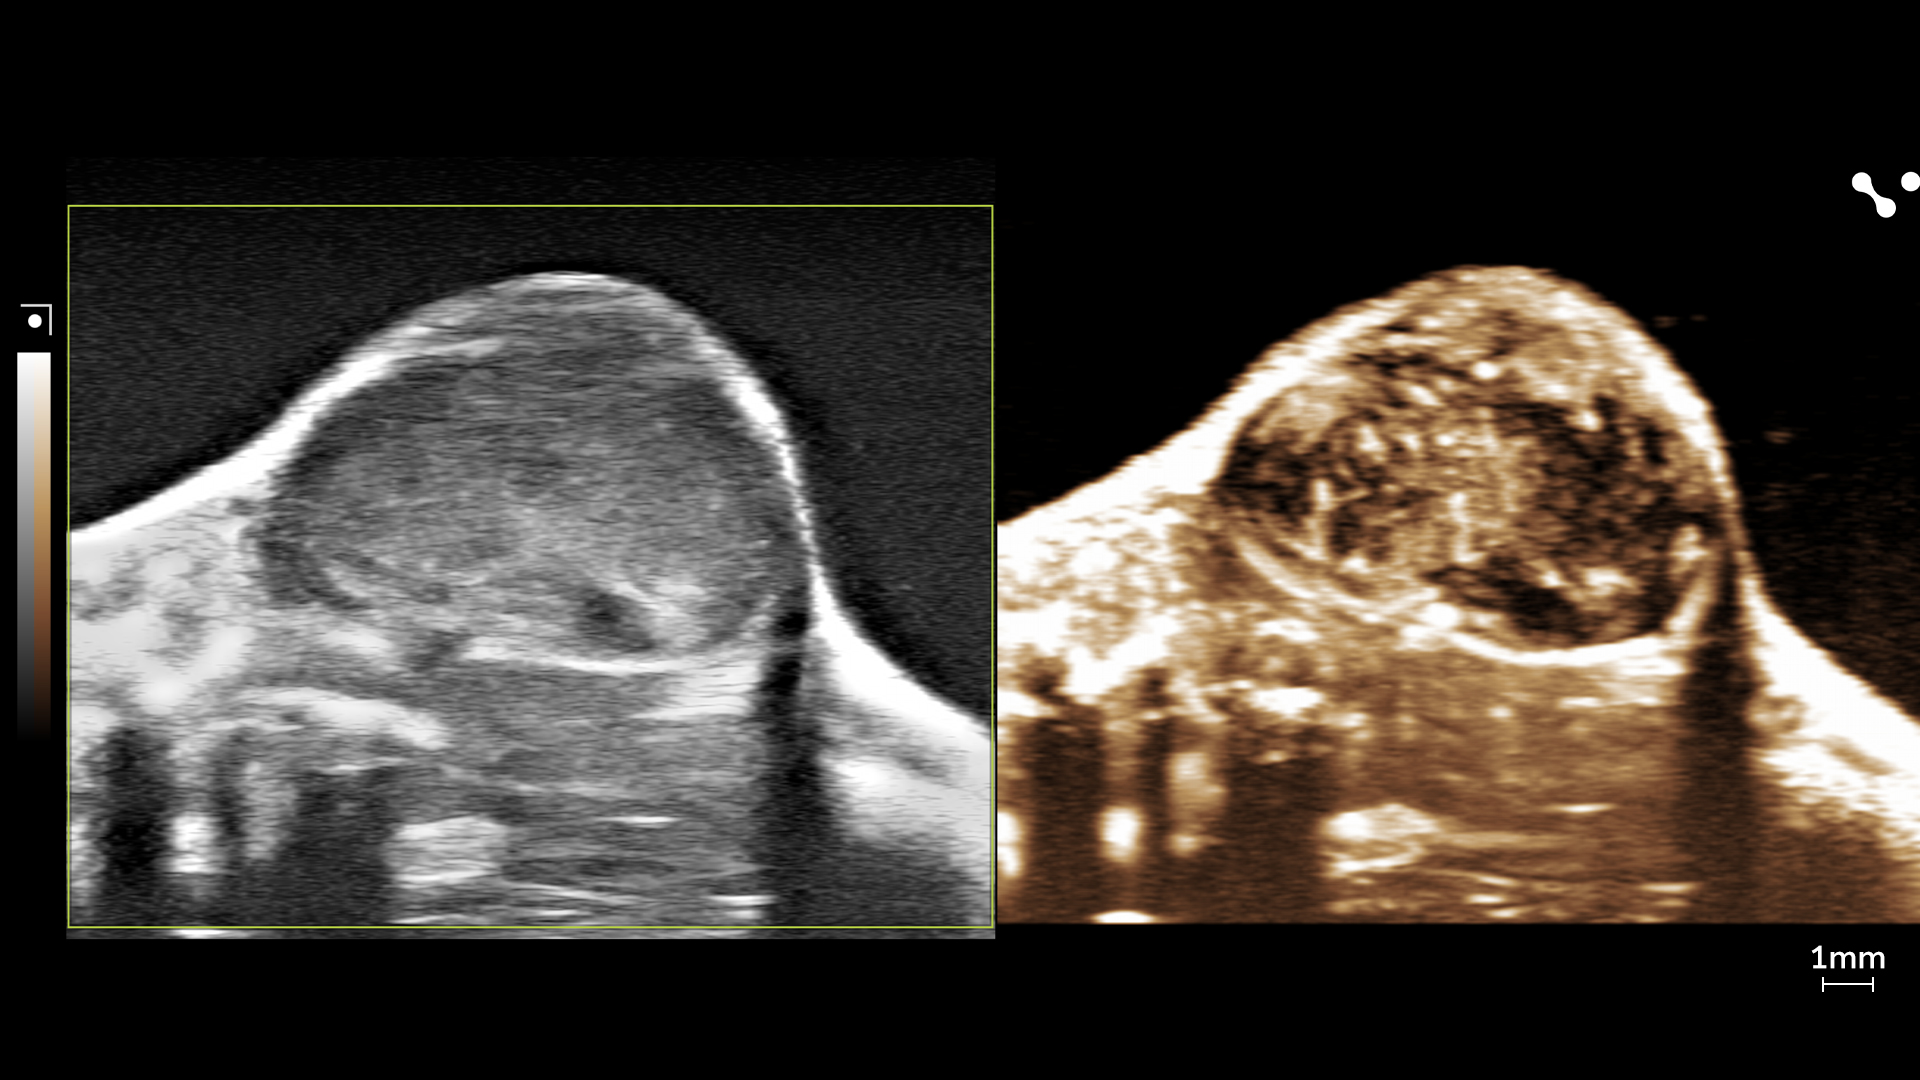

Four ultrasound images showcasing the difference between the control mouse and the NAFLD/MASLD mouse.

Elastography in Action

Easily switch between visualizing stiffness and velocity; see the difference between a healthy liver and a fatty liver.